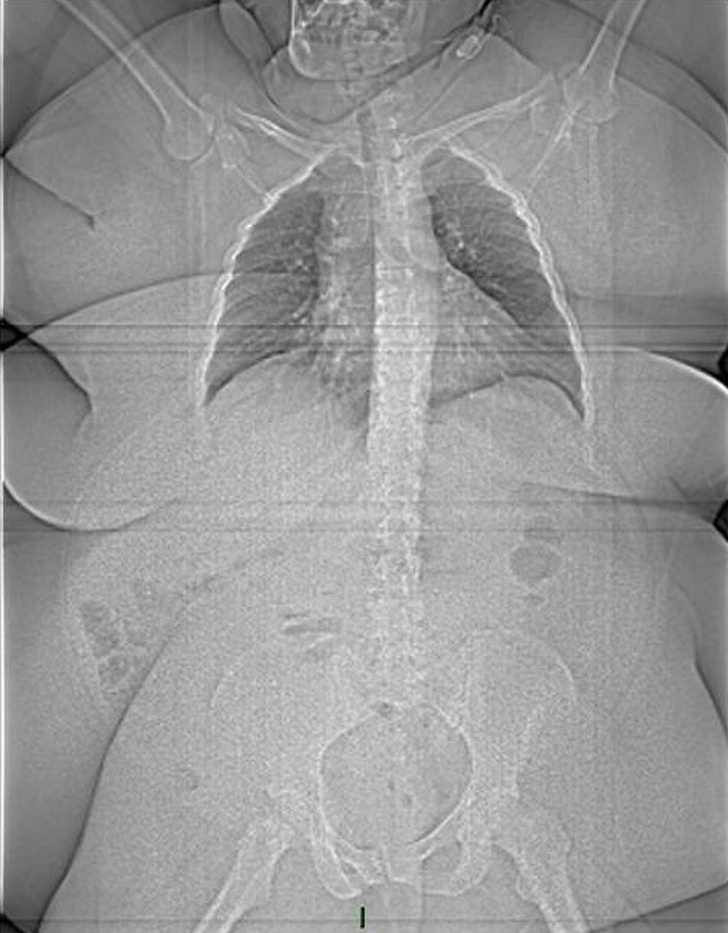

12. Рентгенівський знімок пацієнта вагою 186 кг